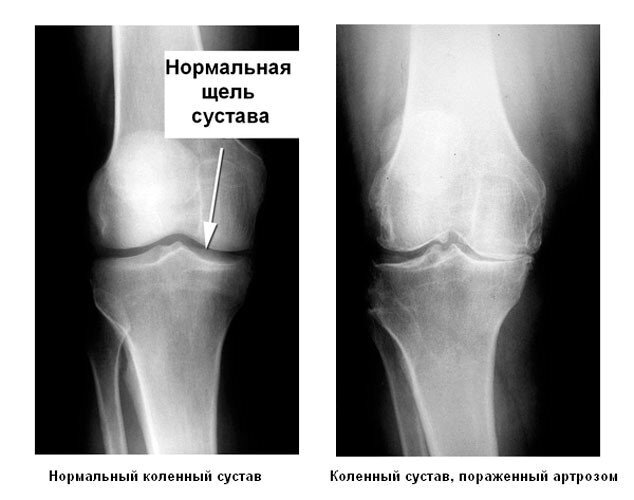

В идеале суставы не должны издавать хруст при движении, но это в идеале! Почему же наши суставы хрустят? Повреждение или эрозия суставной поверхности одна из главных причин возникновения хруста!

R снимок в норме и при патологическом изменении